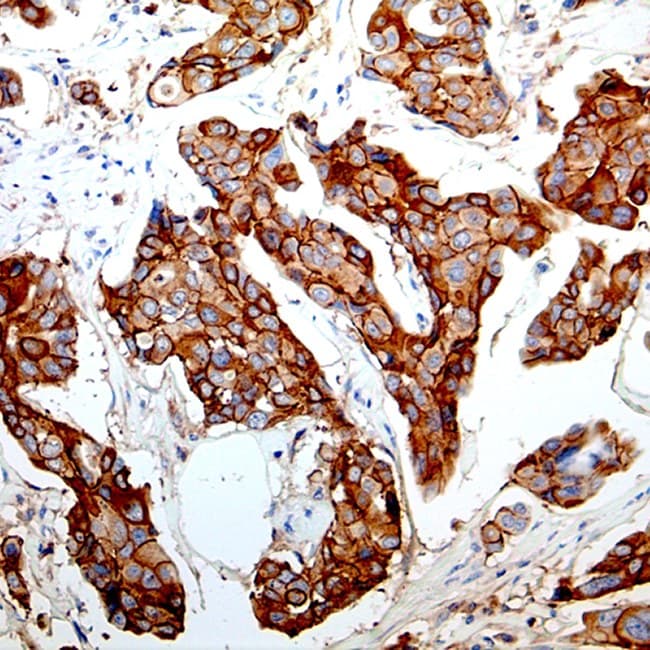

- identifier de manière différentielle le carcinome lobulaire invasif (ILC) par rapport au carcinome canalaire invasif (IDC) du sein, étant donné que la perte de coloration membranaire de l’E-cadhérine est une caractéristique de nombreuses lésions lobulaires.

- Diagnostic différentiel des lésions mammaires lobulaires et canalaires : coloration membranaire claire dans les phénotypes canalaires et coloration membranaire absente/atténuée dans les phénotypes lobulaires classiques ; souvent utilisé conjointement avec les panels p120/β-caténine pour une interprétation concordante.